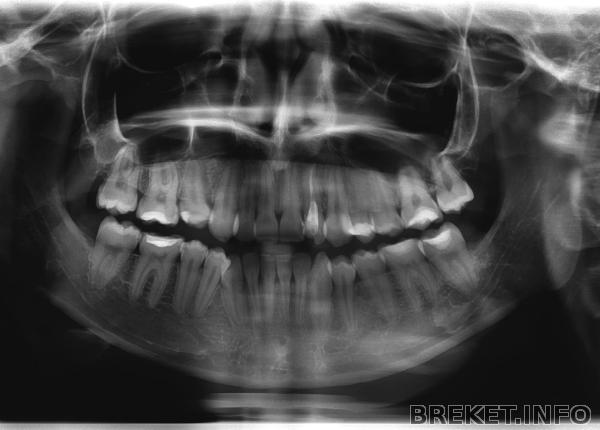

Мне 17,в детстве зубы молочные были нормальными никаких вроде осложнений,правда мне прописали пластины съёмные на зубы,я их не носила потому-что не понимала что будет в последствии и к тому же было очень больно и неудобно(а как объяснишь ребенку что это необходимо),потом у меня нижняя челюсть с каждым годам начинала выпирать помаленьку,что отразилось на подбородоке,он у меня "островатый" теперь,ходила к ортодонту на этой неделе,он сказал что исправить прикус возможно теперь только с помощью операции(резать челюсть)это порядка 250 тыс.руб,ах если бы обратилась туда пораньшеНеужели никак больше?Я не верю И ещё хотела бы узнать,верхние зубы у меня ровные но клыки уходят внутрь немного улыбка неидеальная,хотела бы только на верхнюю челюсть поставить брекеты и тут проблема,чтобы их поставить нужно сначала расширить верхнюю челюсть тоже несъемным аппаратом(3-4 мес).Не повлияет ли это на скулы, черты лица? Даже если повлияет, то на сколько сильно?Вот Снимок

К сожалению (а скорее наверное к счастью) показания (да и противопоказания тоже) к операции на челюстях не определяются по краткому описанию ситуации в интернете. Пусть даже и со снимком зубов